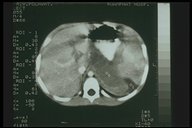

Pancreatic abscess. CT scan showed swelling of the body of pancreas with radiolucent area indicating abscess formation